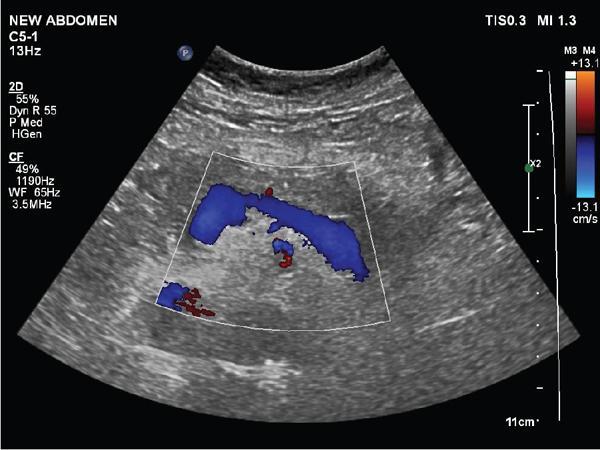

Shrinivas B. Desai, Ritu K. Kashikar, Aman Snehil, Ajay Jhaveri Cirrhosis is a late stage of irreversible scarring of the liver causing abnormality in liver structure and function. Multiple conditions and factors can cause repeated liver damage and scarring ultimately leading to cirrhosis. The most feared complication of liver cirrhosis is the development of hepatocellular carcinoma (HCC). Portal hypertension (PHT) is seen with a variety of conditions but cirrhosis happens to the most important cause. Imaging plays a vital role in noninvasive diagnosis and treatment planning of both cirrhosis and PHT. Liver imaging reporting and data system (LI-RADS) is a standardized reporting system assigning an observation risk of representing HCC. This chapter focuses on discussing aetiologies and imaging of PHT with a lucid review of L1-RADS 2018 version. The portal blood circulation is a unique circulatory circuit as it connects two capillary beds between the liver parenchyma at one end and the gastrointestinal tract and splenic parenchyma at the other end. The portal system ramifies in the liver and ultimately ends in the hepatic sinusoids from where the blood ultimately drains into the inferior vena cava (IVC). The portal vein (PV) originates from the capillary beds in the stomach, intestine and the spleen. The main PV is formed behind the neck of the pancreas by the confluence of the superior mesenteric vein (SMV) and splenic vein. It continues to the porta hepatis where it bifurcates into the left and right branches as it carries nutrient rich but oxygen poor blood to the liver (Fig. 9.9.1). The PV makes up for 75%–80% of the liver’s blood supply while the hepatic artery which arises from the celiac trunk makes up for the remaining 25%. A pathological increase in the portal venous pressure is referred to as PHT. PHT is most often a sequel of chronic parenchymal liver disease and leads to major life-threatening complications due to bleeding from the collateral circulation (most commonly oesophageal varices). Direct measurement of portal pressure (PP) is invasive and often not feasible in most patients and thus imaging plays an important role in the diagnosis of PHT and its complications. The normal portal venous pressure ranges between 5 and 10 mmHg, which is the equivalent of 7–14 cm H2O. The normal hepatic venous pressure gradient (HVPG) is the pressure gradient between the PV and the IVC, is typically 1–5 mmHg. Presence of PHT is indicated by a wedged hepatic venous pressure of more than 5 mmHg. Other definitions include a splenic pressure of more than 15 mmHg or an intraoperative PP of greater than 30 cm H2O. The complications of PHT are seen when HVPG is greater than 10 mmHg and hence this value defines clinically significant PHT. Variceal bleeding is seen with a pressure greater than 12 mmHg. In ideal conditions, the portal circuit is a high flow, low resistance circuit as it has to allow substantial flow rates of 700–1000 mL/min to the hepatic parenchyma from the gastrointestinal tract. Anatomical changes in the organization of the hepatic lobule can result in rise in the portal resistance. These can occur in the form of collagen deposition in the space of Disse, fibrotic scars formed due to regenerative nodule (RN) formation, loss of normal elasticity of the endothelium and distal venous thrombosis. Changes in splanchnic haemodynamics due to factors that increase splanchnic blood flow and increase in intrahepatic vascular resistance due to transformation of stellate cells into myofibroblasts also contribute to the increase in PP gradient. In Western countries, alcoholic cirrhosis and viral cirrhosis are the leading causes of PHT and oesophageal varices. The viral causes form majority of cases leading to cirrhosis and PHT in the Far East and Middle Eastern countries while Schistosomiasis remains an important cause in the African countries. Worldwide, nonalcoholic steatohepatitis (NASH) and hepatitis C are the emerging causes of chronic liver disease (CLD) and PHT. PHT can be classified as cirrhotic and noncirrhotic depending on whether it is associated with cirrhosis or not. This distinction is important as noncirrhotic causes like PV thrombosis are at high risk of development of bleeding but tend to have a better chance of surviving a variceal bleed than a patient with decompensated alcoholic cirrhosis due to preserved hepatic synthetic functions in the former. PHT can also be classified on the basis of the location of the pathology into prehepatic, hepatic and posthepatic causes. Hepatic causes can further be divided into presinusoidal, sinusoidal and postsinusoidal. The causes of portal hypertension have been denoted in Table 9.9.1. The direct measurement of the PP by measuring the HVPG is invasive, expensive not readily available in all patients. Thus, imaging plays an important role in the diagnosis of PHT. Various modalities are used for the imaging diagnosis of PHT. Ultrasonography (USG) and Doppler evaluation have the advantage of being inexpensive, readily available and bedside modality (Table 9.9.2). The role of ultrasound and Doppler in imaging of PHT is to: Grey scale imaging is useful in evaluating the splenoportal anatomy. The evaluation should begin with the liver morphology. Signs of cirrhosis like nodularity of the liver surface with relative atrophy of the right lobe and prominence of the left lobe and caudate should be looked for. Hepatic echotexture appears coarse and more echogenic (Table 9.9.3). Increase in portal venous diameter is a sign of PHT (Fig. 9.9.2). Portal venous diameter of more than 13 or 15 mm has low sensitivity for diagnosing PHT of only 40%–12.5%, respectively. Absolute measurement of the portal diameter as a sign of PHT is also fallacious as in presence of collateral circulation or hepatofugal flow; there may actually be a decrease in the PV diameter. Therefore, a more accurate sign is respiratory variation of PV diameter. An increase in PV diameter of less than 20% with deep inspiration has been reported to indicate PHT with a sensitivity of 80% and specificity of 100%. This has been reported to be an accurate indicator of cirrhosis. Hepatic vein straightness, uniformity of vein wall echogenicity and visualization of at least 1 cm segment of the hepatic vein are the parameters used for evaluation. Splenomegaly is defined as bipolar splenic diameter of greater than 12 cm or largest splenic cross-sectional area passing through the hilum of greater than 45 cm2, and occurs secondary to PHT (Fig. 9.9.3). A total of 65%–80% patients with cirrhosis have splenomegaly on ultrasound. Patients with cirrhosis due to viral hepatitis and primary biliary cirrhosis show splenomegaly more frequently than those with alcoholic cirrhosis. This is an accurate sign of PHT. USG is extremely sensitive with respect to detecting subclinical ascites. Perihepatic space is the most usual site of visualization of minimal ascites. In normal subjects, this ratio is approximately 0.07 and a value above 0.1 suggests the diagnosis of PHT with a 95% sensitivity and specificity. The normal spectral waveform of the hepatic artery is a low resistance flow pattern with forward flow in diastole and a resistivity index in the range of 0.5–0.7. In PHT, the resistivity index of the hepatic artery increases with high resistance flow pattern due to increased peripheral vascular resistance. Resistance index (RI) > 0.78 in the intrahepatic branches of the hepatic artery has been reported to have a sensitivity of 50% and a specificity of 100% for the detection of PHT (Fig. 9.9.11). Pulsatility index (PI) > 1.05 suggests severe PHT with a sensitivity of 86% and specificity of 88% (Fig. 9.9.11). Patency of hepatic veins should be evaluated to rule out Budd–Chiari syndrome as a cause of PHT. The normal hepatic venous waveform (HVW) reflects right atrial activity and this results in a triphasic waveform with one positive and two negative waves. In PHT, this waveform becomes monophasic or biphasic. A monophasic HVW has a sensitivity and specificity of 74% and 95%, respectively, in the diagnosis of severe PHT (Fig. 9.9.12). Dilatation of the splanchnic veins – the SMV and the splenic vein – more than 11 mm are suggestive of PHT with a sensitivity and specificity of 72% and 100%, respectively. A reduction in the respiratory variation of the splenic vein and SMV to less than 40% had a sensitivity and specificity of 79.7% and 100%, respectively, for the diagnosis of PHT (Fig. 9.9.13). The splenic artery reveals an increase in the resistivity index and an RI of >0.63 and a PI of >1 have a sensitivity and specificity of 84.6% and 70.4% for the diagnosis of PHT. Presence of portosystemic collaterals like patent paraumbilical vein, dilated left gastric and short gastric veins are 100% specific sign for PHT (Figs. 9.9.14–9.9.16). Recanalization of the paraumbilical vein, known as the Cruveilhier–Baumgarten syndrome is observed in 43% of patients with PHT, and this is the easiest collateral to assess during the US examination. Various portosystemic collaterals that occur in PHT have been discussed in details in subsection on CT findings in PHT. No Doppler parameter is considered reliable enough to measure PP with sufficient accuracy for use in clinical practice. Oesophageal varices are often present in patients with portosystemic collaterals. Appearance or increase in number of collaterals along with splenomegaly has a high association with variceal formation and growth. USG helps in diagnosis of prehepatic causes like portal stenosis or thrombosis by demonstrating the patency and morphology of the splenoportal system. Arteriovenous fistulae and tumours causing vascular thrombosis as aetiology can be readily detected. USG helps in diagnosis of features of cirrhosis and thus helps differentiate noncirrhotic causes of PHT. USG allows diagnosis of fatty liver disease, which is an emerging cause of cirrhosis. Among the posthepatic causes, USG aids in establishing the diagnosis of Budd–Chiari syndrome by demonstrating the patency and morphology of the IVC and hepatic veins. Owing to the inability of CT to detect flow direction, portal flow rates or pressure gradients, CT is not the primary modality in diagnosis of PHT. Similar to USG dilatation of portosystemic system is a feature of PHT (Fig. 9.9.17). Changes in cirrhosis if present can be seen in the form of surface nodularity, nodules and fibrous septae. CT plays an important role in diagnosis of portal venous thrombosis and evaluating its extent. An acute thrombus is seen as a hypodense filling defect in the vessel causing distension of the venous lumen. Surrounding fat stranding can be seen. A chronic thrombus appears as an eccentric filling defect usually along the wall and is often associated with decrease in vessel diameter. Calcification may be seen in chronic thrombi. Multidetector computed tomography (MDCT) is a useful tool to evaluate portosystemic collateral circulation and recognize complications of PHT. 3D angiography can help understand portal venous and complex variceal anatomy and plan treatment. The various portosystemic collaterals are discussed below. They can be classified into those draining into superior vena cava (SVC) and those draining into the IVC. Magnetic resonance imaging (MRI) is a noninvasive modality used in the evaluation of PHT without the use of ionising radiation. It provides evaluation of parenchymal abnormalities, collaterals and characterization of tumours (Fig. 9.9.28). Spin echo sequences allow characterization of liver masses and liver parenchyma. Loss of flow void allows for detection of thrombosis. Time-of-flight (TOF) angiography is useful in assessing the portal venous system and allows for successful detection of PV thrombosis. The disadvantages of TOF are motion artefacts caused by breathing, long acquisition times and incomplete coverage of the portal venous system. Novel imaging techniques include phase contrast, T1 mapping and magnetic resonance elastography (MRE). The advantage of phase contrast over TOF imaging is that phase contrast imaging acquires information regarding the flow direction in addition to the information regarding the flow velocity. On-phase contrast images signal within vessel is hyperintense when flow is cranial and hypointense when flow is caudal. Look-Locker imaging technique using gradient echo (GRE) MRI sequences with inversion recovery pulse is used to quantify fibrosis by measuring precontrast T1 relaxation times. Interventions in PHT can be aimed at diagnosis or more commonly at management of complications of PHT. HVPG measurement, which is the gold standard for the diagnosis of PHT, can be achieved through cannulation of the PV. Transjugular hepatic biopsy is another diagnostic invasive technique that also allows indirect measurement of PP. Disadvantages include deterioration of hepatic function caused by diversion of portal venous blood flow and shunt dysfunction. TIPSS is contraindicated in patients with congestive heart failure, severe pulmonary hypertension, severe tricuspid regurgitation and hepatic failure. In this technique, a catheter is advanced from the femoral vein into the outlet of the gastrorenal, usually in the region of the left renal vein. The shunt is then occluded with a balloon and sclerosant is injected retrograde to occlude the gastric varices. Histological development of RNs surrounded by fibrous septae in response to chronic liver injury, progressing PHT and end-stage liver disease is termed as cirrhosis. Although initially considered an end-stage phenomenon in CLD, recent evidence suggests that the histological fibrosis can be reversible in early stages with the initiation of specific therapies, for example, in viral cirrhosis with the initiation of antiviral therapy. The one-year mortality rate in cirrhosis varies widely from 1% to 57% depending on the occurrence of complications. Cirrhosis can have a wide variety of causes ranging from congenital to acquired and infectious to noninfectious. It is also a major aetiologic risk factor for the development of HCC. Imaging plays an important role in aetiologic diagnosis of this diverse entity as well as in the diagnosis and management of its complication and surveillance for oncological transformation.